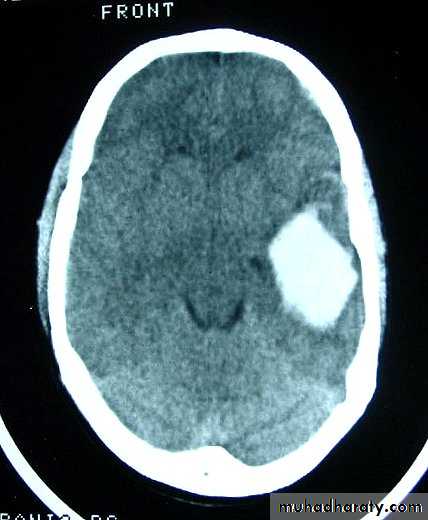

c. Intracerebral Haematoma

This is the least common of traumatic haematoma.

They are due to areas of traumatic contusion coalescing into a contusional haematoma.

Disrupted cerebral tissue release thromboplastins that potentiate haemorrhage.

CT scan: appear as hyperdence lesions with associated mass effect and midline shift.

Large intracerebral haematomas should be evacuated unless the patient’s neurological state is improving.

Small inracerebral haematomas may not require removal, but be aware that they can expand.